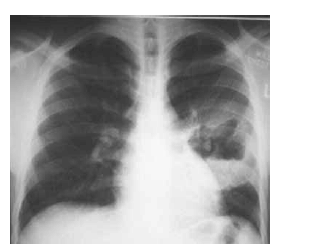

Um menino de quatro anos de idade, morador de uma instituição de apoio a menores abandonados, foi levado a uma emergência pediátrica com história de febre alta havia três dias. Nesse período, o quadro clínico evoluiu para dificuldade respiratória e gemência. No exame físico da criança, foram constatados, além de febre e dificuldade respiratória, palidez, aspecto toxêmico, sinais de desidratação e uma lesão pustulosa tensa no membro inferior direito. A radiografia de tórax do paciente apresentou o seguinte aspecto.

Nesse caso, a criança deverá receber tratamento específico à base de oxacilina.